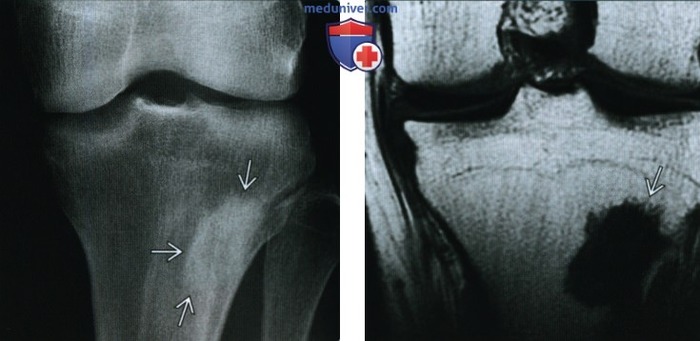

Дифференциальная диагностика

Эностоз необходимо дифференцировать с другими образованиями костной ткани, такими как:

• Остеоид-остеома.

• Остеобластные метастазы.

• Склерозирующие дисплазии костей.

Для уточнения диагноза могут быть использованы дополнительные методы визуализации, такие как КТ или МРТ. В сомнительных случаях может потребоваться биопсия.

МРТ

Варианты эностозов на КТ И МРТ.